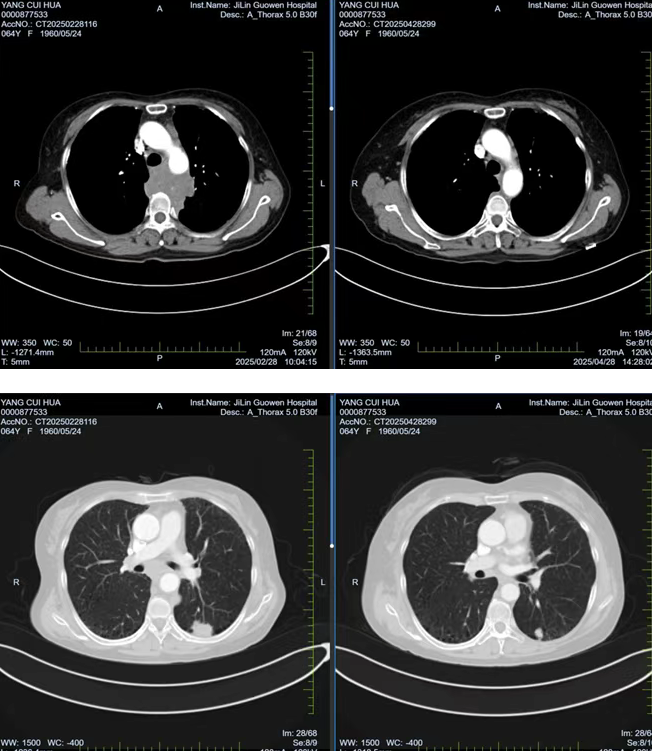

張阿姨因胸背部疼痛持續(xù) 1個(gè)月且逐漸加重,在當(dāng)?shù)蒯t(yī)院檢查時(shí)發(fā)現(xiàn)左肺存在腫物,初步考慮為惡性腫瘤。經(jīng)熟人介紹,了解到我院在腫瘤??萍膊≈委煼矫娴膬?yōu)勢(shì)后,該患者前往我院就診。胸部腫瘤放化療二科為其安排了 PET/CT 檢查,并對(duì)左側(cè)鎖骨上腫大淋巴結(jié)進(jìn)行穿刺活檢,最終明確診斷為左肺下葉高級(jí)別神經(jīng)內(nèi)分泌癌,臨床分期為 cT1cN3M0 IIIb 期,且縱隔轉(zhuǎn)移淋巴結(jié)已侵犯椎體,患者因劇烈疼痛,生活質(zhì)量受到嚴(yán)重影響。